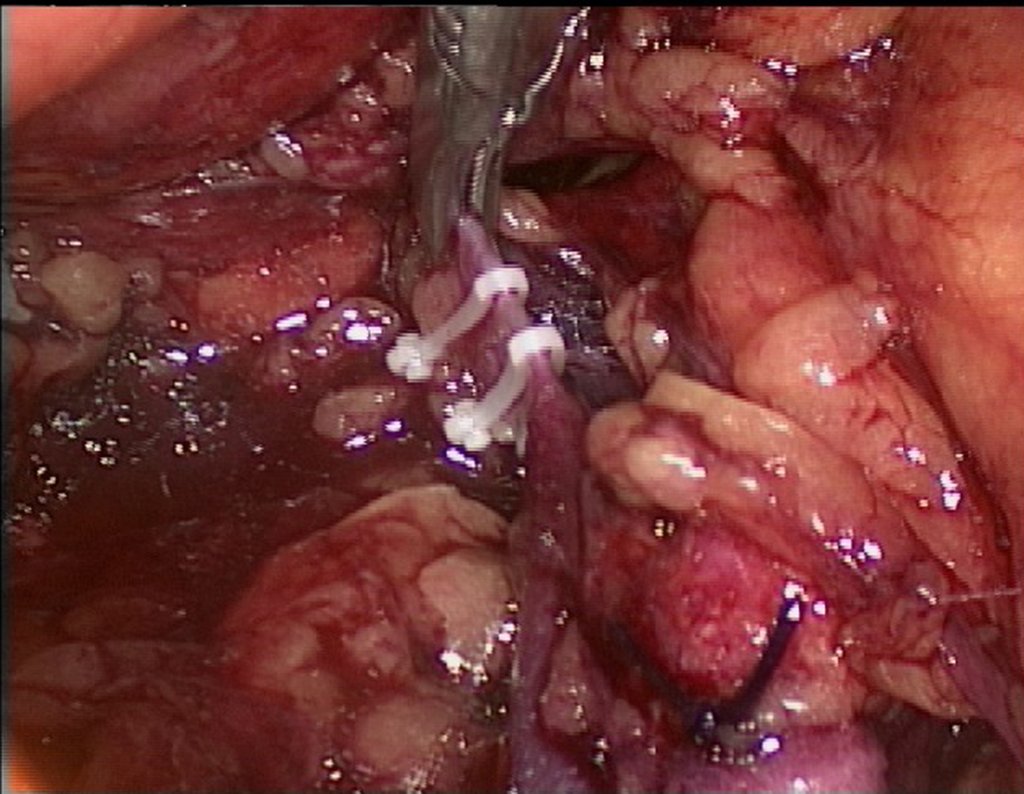

Dissecção e Ligadura de Vasos: A equipe da laparoscopia iniciou a abordagem dissecando os vasos ilíacos e pélvicos, proporcionando passagem segura para as serras flexíveis. O retroperitônio foi acessado e os vasos anteriores ao tumor foram ligados e cauterizados.

Passagem do Cateter de Ressecção: Um cateter de ressecção foi introduzido através do portal videolaparoscópico, transfixando o sacro para passagem da serra de Gigli. Este cateter foi cuidadosamente posicionado para garantir a segurança durante a osteotomia posterior.

Osteotomia e Ressecção do Tumor: A serra de Gigli foi utilizada para ressecar a lesão, seguida pela remoção da peça tumoral. A incisão foi ampliada conforme necessário para melhor visualização e manipulação da lesão.

Hemostasia e Sutura: Após a ressecção, hemostáticos de partes moles foram aplicados e a região foi suturada. A área operada foi limpa e preparada para o fechamento final, garantindo controle adequado do sangramento.